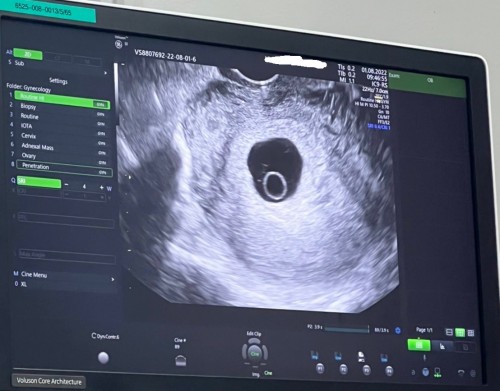

ตั้งครรภ์7สัปดาห์2วัน เลือดออกสีน้ำตาลเข้ม มีปวดท้องนิดหน่อย อันตรายมั้ย อัลตร้าซาวด์พบตัวอ่อนแต่น้องหัวใจเต้นเบามาก

มีภาวะแท้งคุกคาม กังวลมากค่ะ